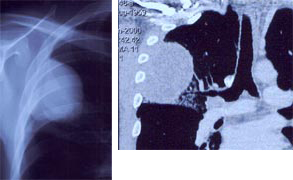

左写真:胸部エックス写真で、黒い部分が肺です。中央から向かって左に飛び出た部分が心臓です。

中央写真:向かって左側に白い部分があります。これは右肺がんです。

右写真:切除標本の切離面です。茶色か黒い部分が正常の肺で、乳白色の部分が肺がんです。気管支の中に入り込んでいるのが分かります。